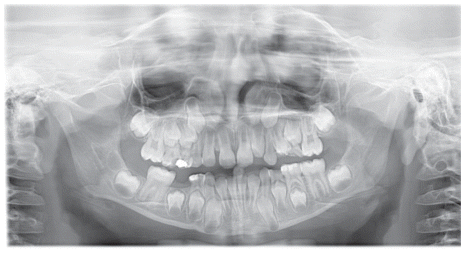

The patient was a young female presenting with a Class III dento-skeletal malocclusion, which was treated using the AMCOP® TC appliance. A comprehensive diagnostic protocol was carried out both before and after treatment, including orthopantomography (Figure 2–3), postero-anterior teleradiography (Figures 4, 5), latero-lateral cephalometric radiography (Figures 6, 7), cephalometric analysis (Tables 1, 2), as well as extraoral (Figures 8, 9) and intraoral photographs (Figures 10, 11). The extraoral examination revealed an edge-to-edge incisal relationship and the presence of a midline diastema. Pre-treatment cephalometric analysis (Deltadent® Lana, Bolzano, Italy) confirmed the diagnosis of a skeletal Class III malocclusion. The treatment plan involved the use of the AMCOP® TC appliance. The patient was instructed to wear the device for two hours in the afternoon and throughout the night for the first six months, followed by nighttime use only for an additional six months. Upon completion of the treatment, the patient achieved a Class I occlusion, with correction of both overjet and overbite. Additionally, the device facilitated tongue re-education and contributed to the postural realignment of the first cervical vertebra.